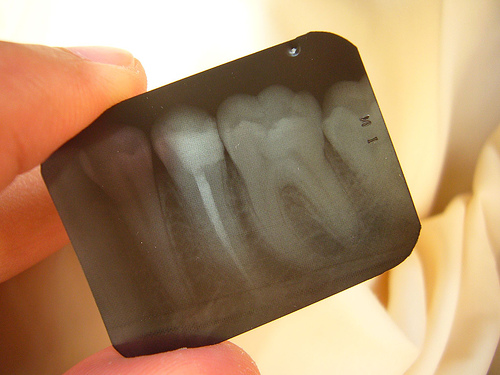

X-rays or Radiographs

Radiography should be avoided, especially in the first trimester, even though dental radiography is unlikely to be a significant risk unless the beam is directed to the fetus. When an apron is used in dental radiography, gonadal and fetal exposure is negligible. It has been estimated that two periapical dental X-rays give an exposure less than that due to natural radiation for 1 day. Nevertheless, of radiography is essential, patients must wear a lead apron and exposure must be minimal. MRI (magnetic resonance imaging) is best avoided during the first trimester.